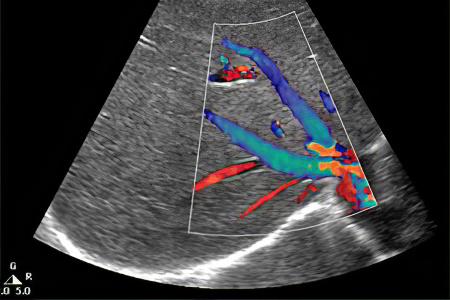

Ранее для диагностики тромбоза почечных вен широко применялась ангиография. Однако современные подходы в лечении предполагают использование других методов. Предпочтение отдается мультиспиральной компьютерной томографии. Этот метод особенно рекомендуется при подозрении на тромбоз почечных вен, так как он не требует введения контрастного вещества. Это важно, поскольку все контрастные препараты могут иметь нефротоксический эффект, негативно влияя на состояние почек, которые могут уже испытывать функциональные нарушения. Поэтому методы диагностики должны быть максимально щадящими.

Не следует недооценивать и ультразвуковое исследование. Доплеровская ультрасонография может быть использована для выявления тромбоза почечных вен, однако стоит помнить о высокой вероятности получения ложноотрицательных результатов.